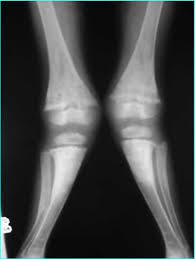

Göğüs kafesinde ve omurgada şekil bozuklukları görülür.Bu çocukların oturma ve yürümeleri gecikir.Yürüdükleri zaman ”O Bacak” veya ”X Bacak” denilen eğilmeler olur.Terleme ileri derecede artmış olu başın arka kısmındaki saçlarda seyrekleşme dikkati çeker.Vücudun enfeksiyonlara karşı direnci de düşük olduğu için üst solunum yolu hastalıkları ve zatürre sık görülür.Süt çocuklarında kandaki kalsiyum düşüklüğü,bazen bebeğin havale geçirmesine neden olabilir.